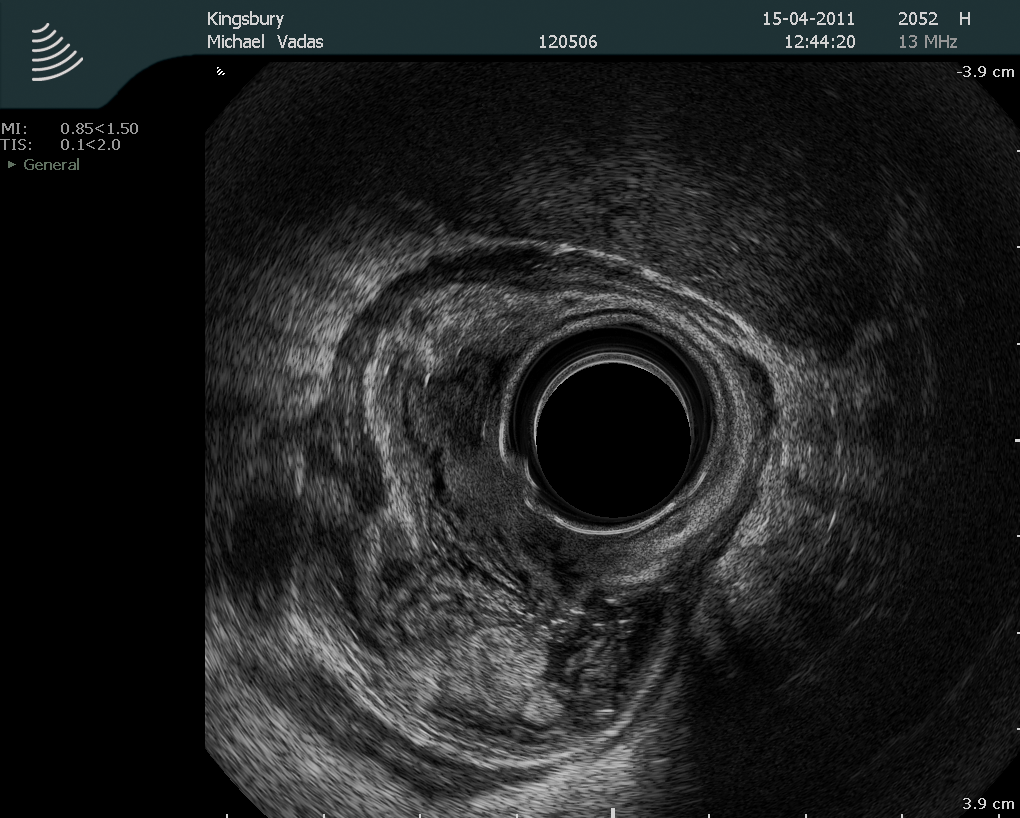

Colorectal cancer affects approximately 1:20 of the population and in South Africa is largely managed by general surgeons. Management of this disease has undergone very significant changes over the last two decades. Until very recently, only two academic general surgery departments included a specialist colorectal unit, and this remains so in the majority of our universities. This has resulted in a generation of surgical graduates who are unfamiliar with, and unskilled in current best management practices for this disease. Rectal cancer is particular challenging and attracts extremely high morbidity and mortality, with poor oncological outcomes. Repeatedly, outcome has been shown to be worse in the hands of generalists, rather than specialist colorectal surgeons, of whom there are very few in the country. This review presents the most important advances of the last 20 years and highlights current controversies and frontiers.